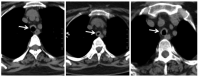

A 50-year-old female patient was evaluated at our center in February 2016 with history of hearing loss, inflammatory arthritis, and saddle nose for four years and new-onset worsening of hoarseness of voice, cough and breathlessness for three months. She was being treated as GPA based on clinical features and anti-myeloperoxidase (MPO) positivity with oral steroids and weekly methotrexate of 22.5 mg. Further evaluation showed normal complete blood count but raised erythrocyte sedimentation rate with normal urine examination, renal functions and liver functions. Chest X-ray did not show any infiltrates. Cardiac evaluation was normal. High-resolution computed tomography (HRCT) of the chest with neck cuts showed circumferential thickening of trachea (Figure 1).